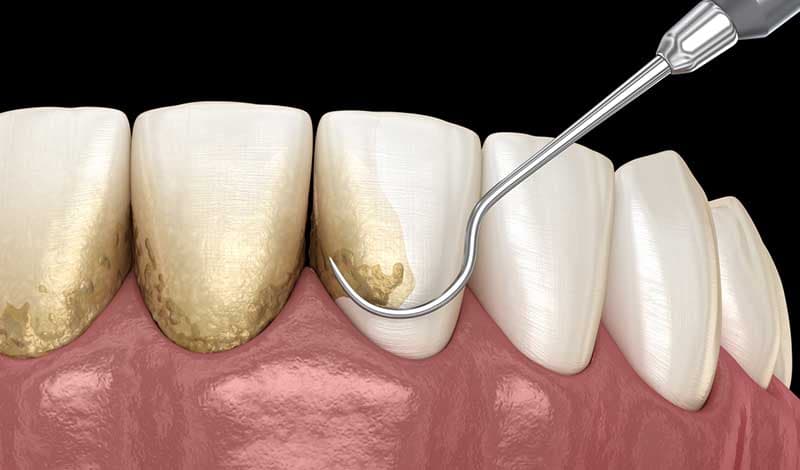

Rutin kontroller ve diş taşı temizliği.